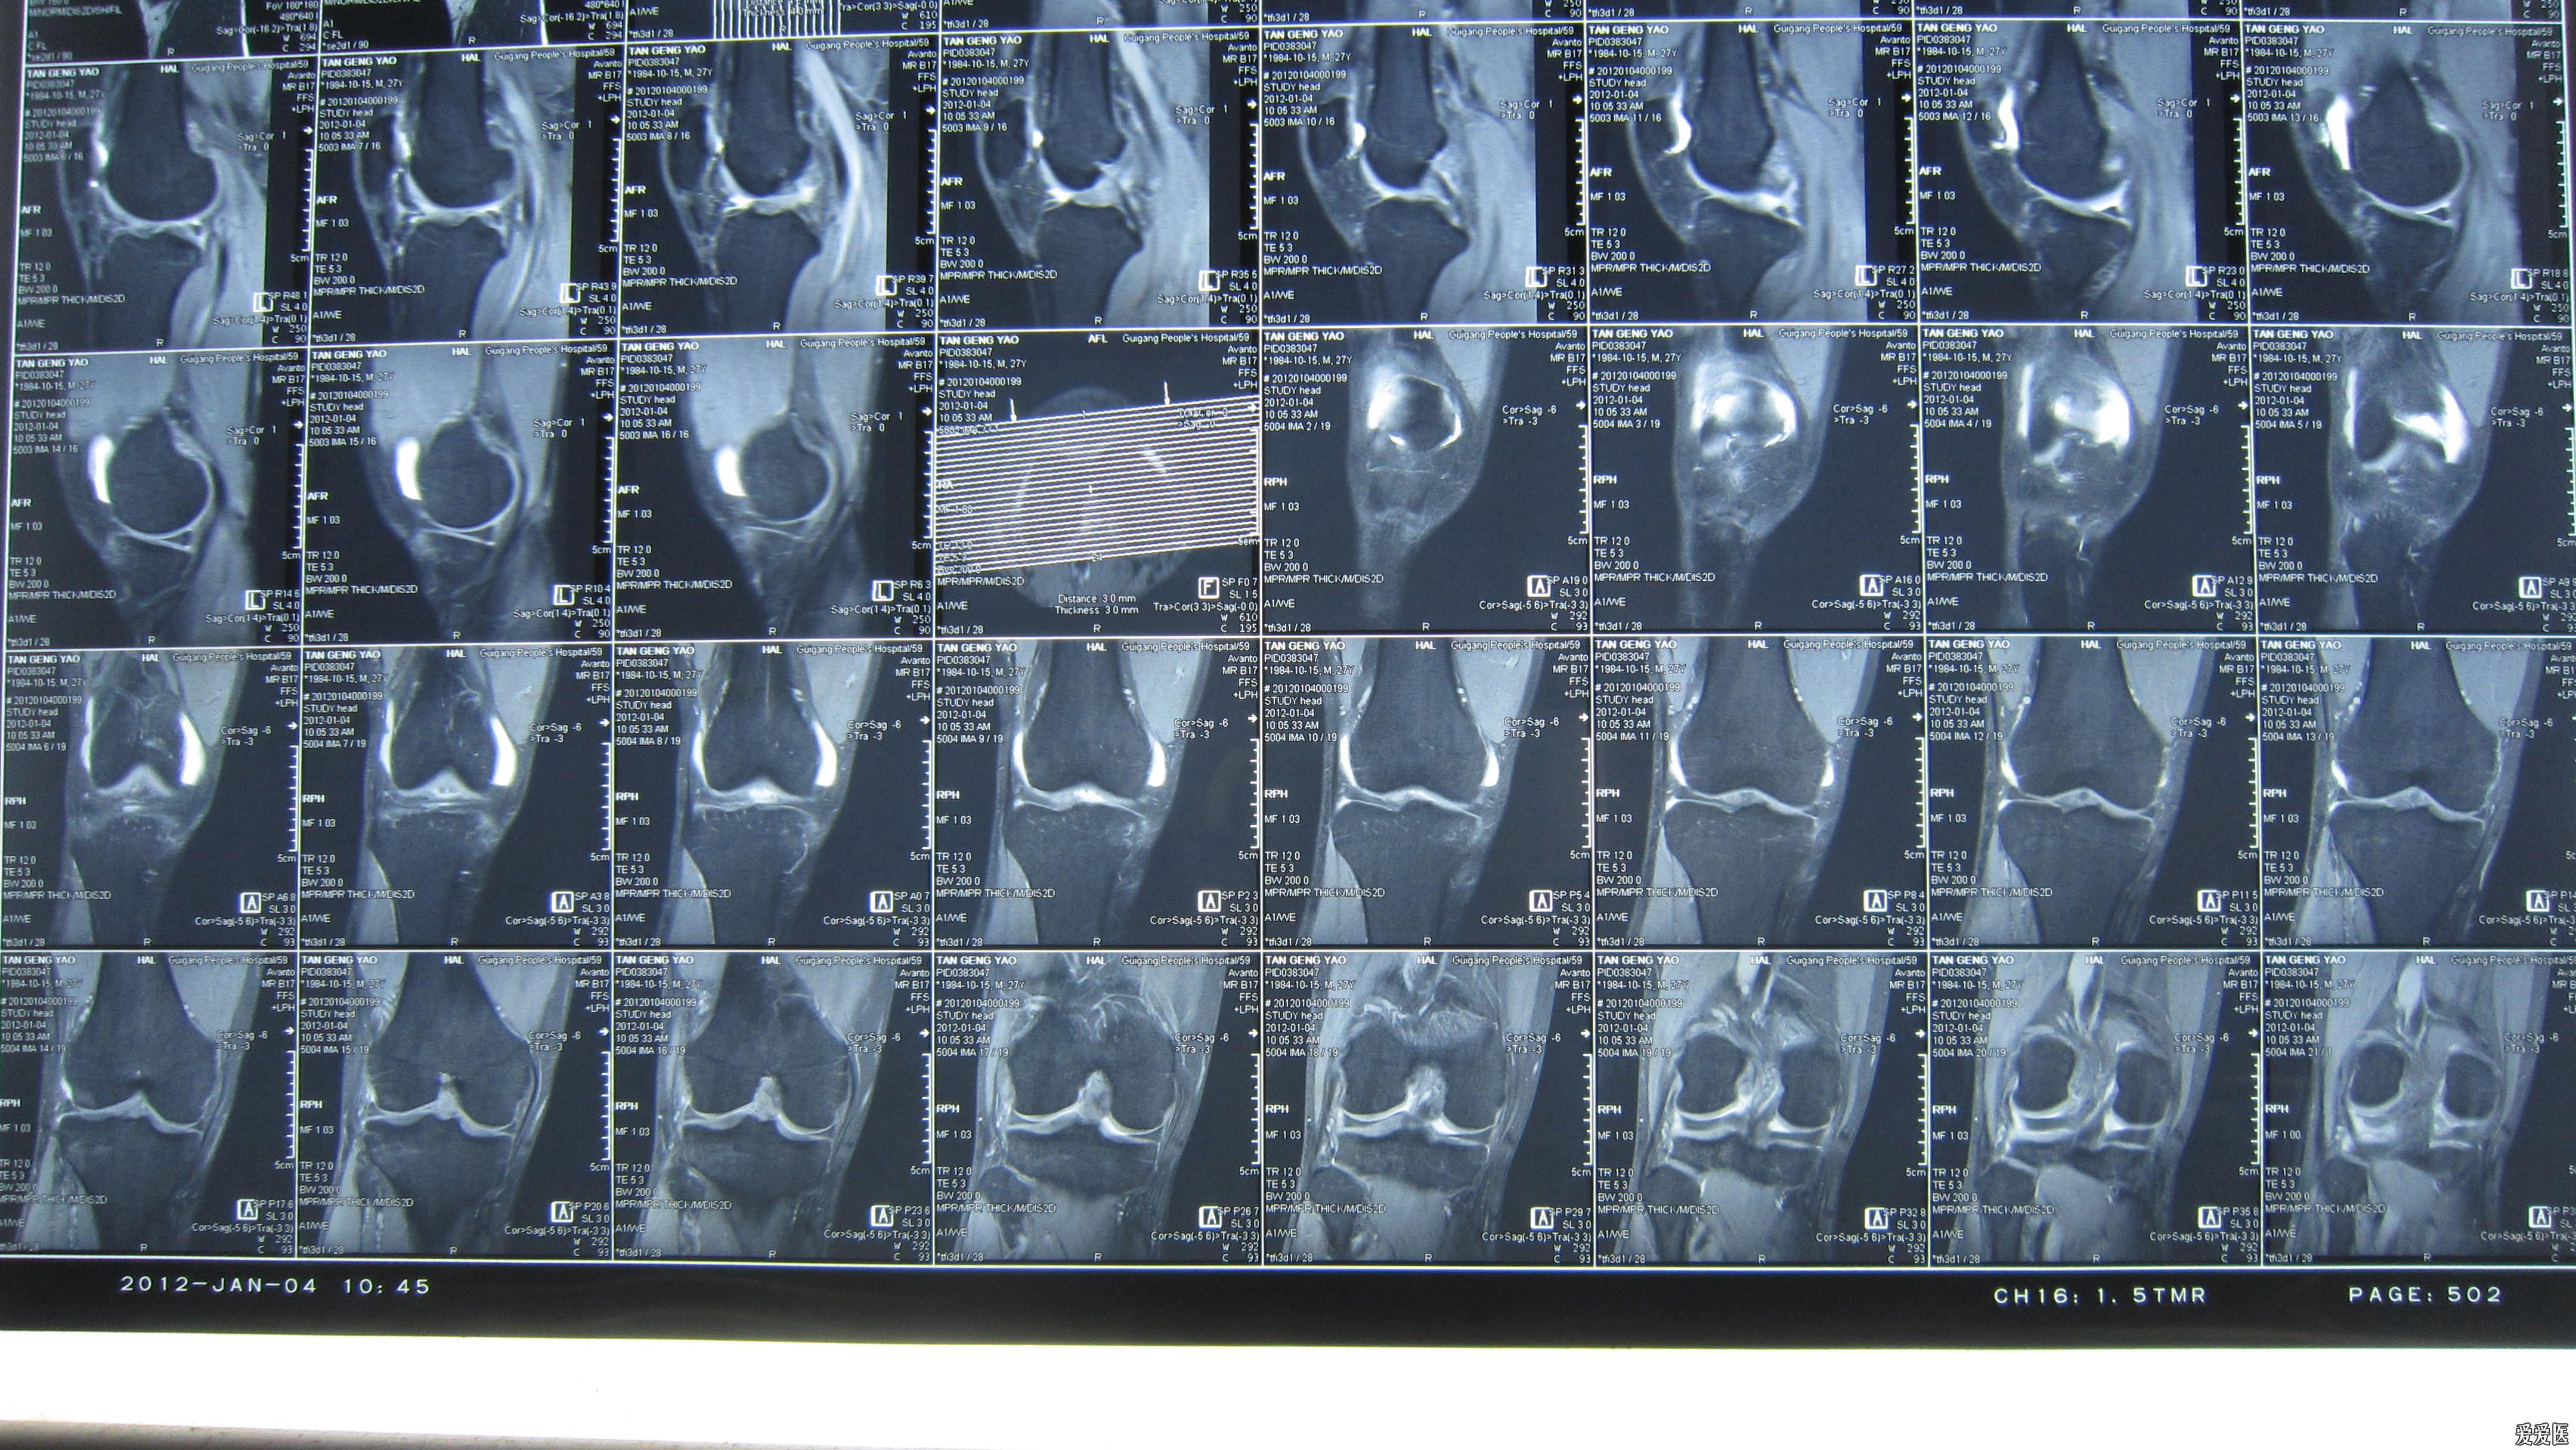

诊断:左侧小腿开放伤,皮下软组织潜行游离伤,左膝关节前交叉韧带损伤.